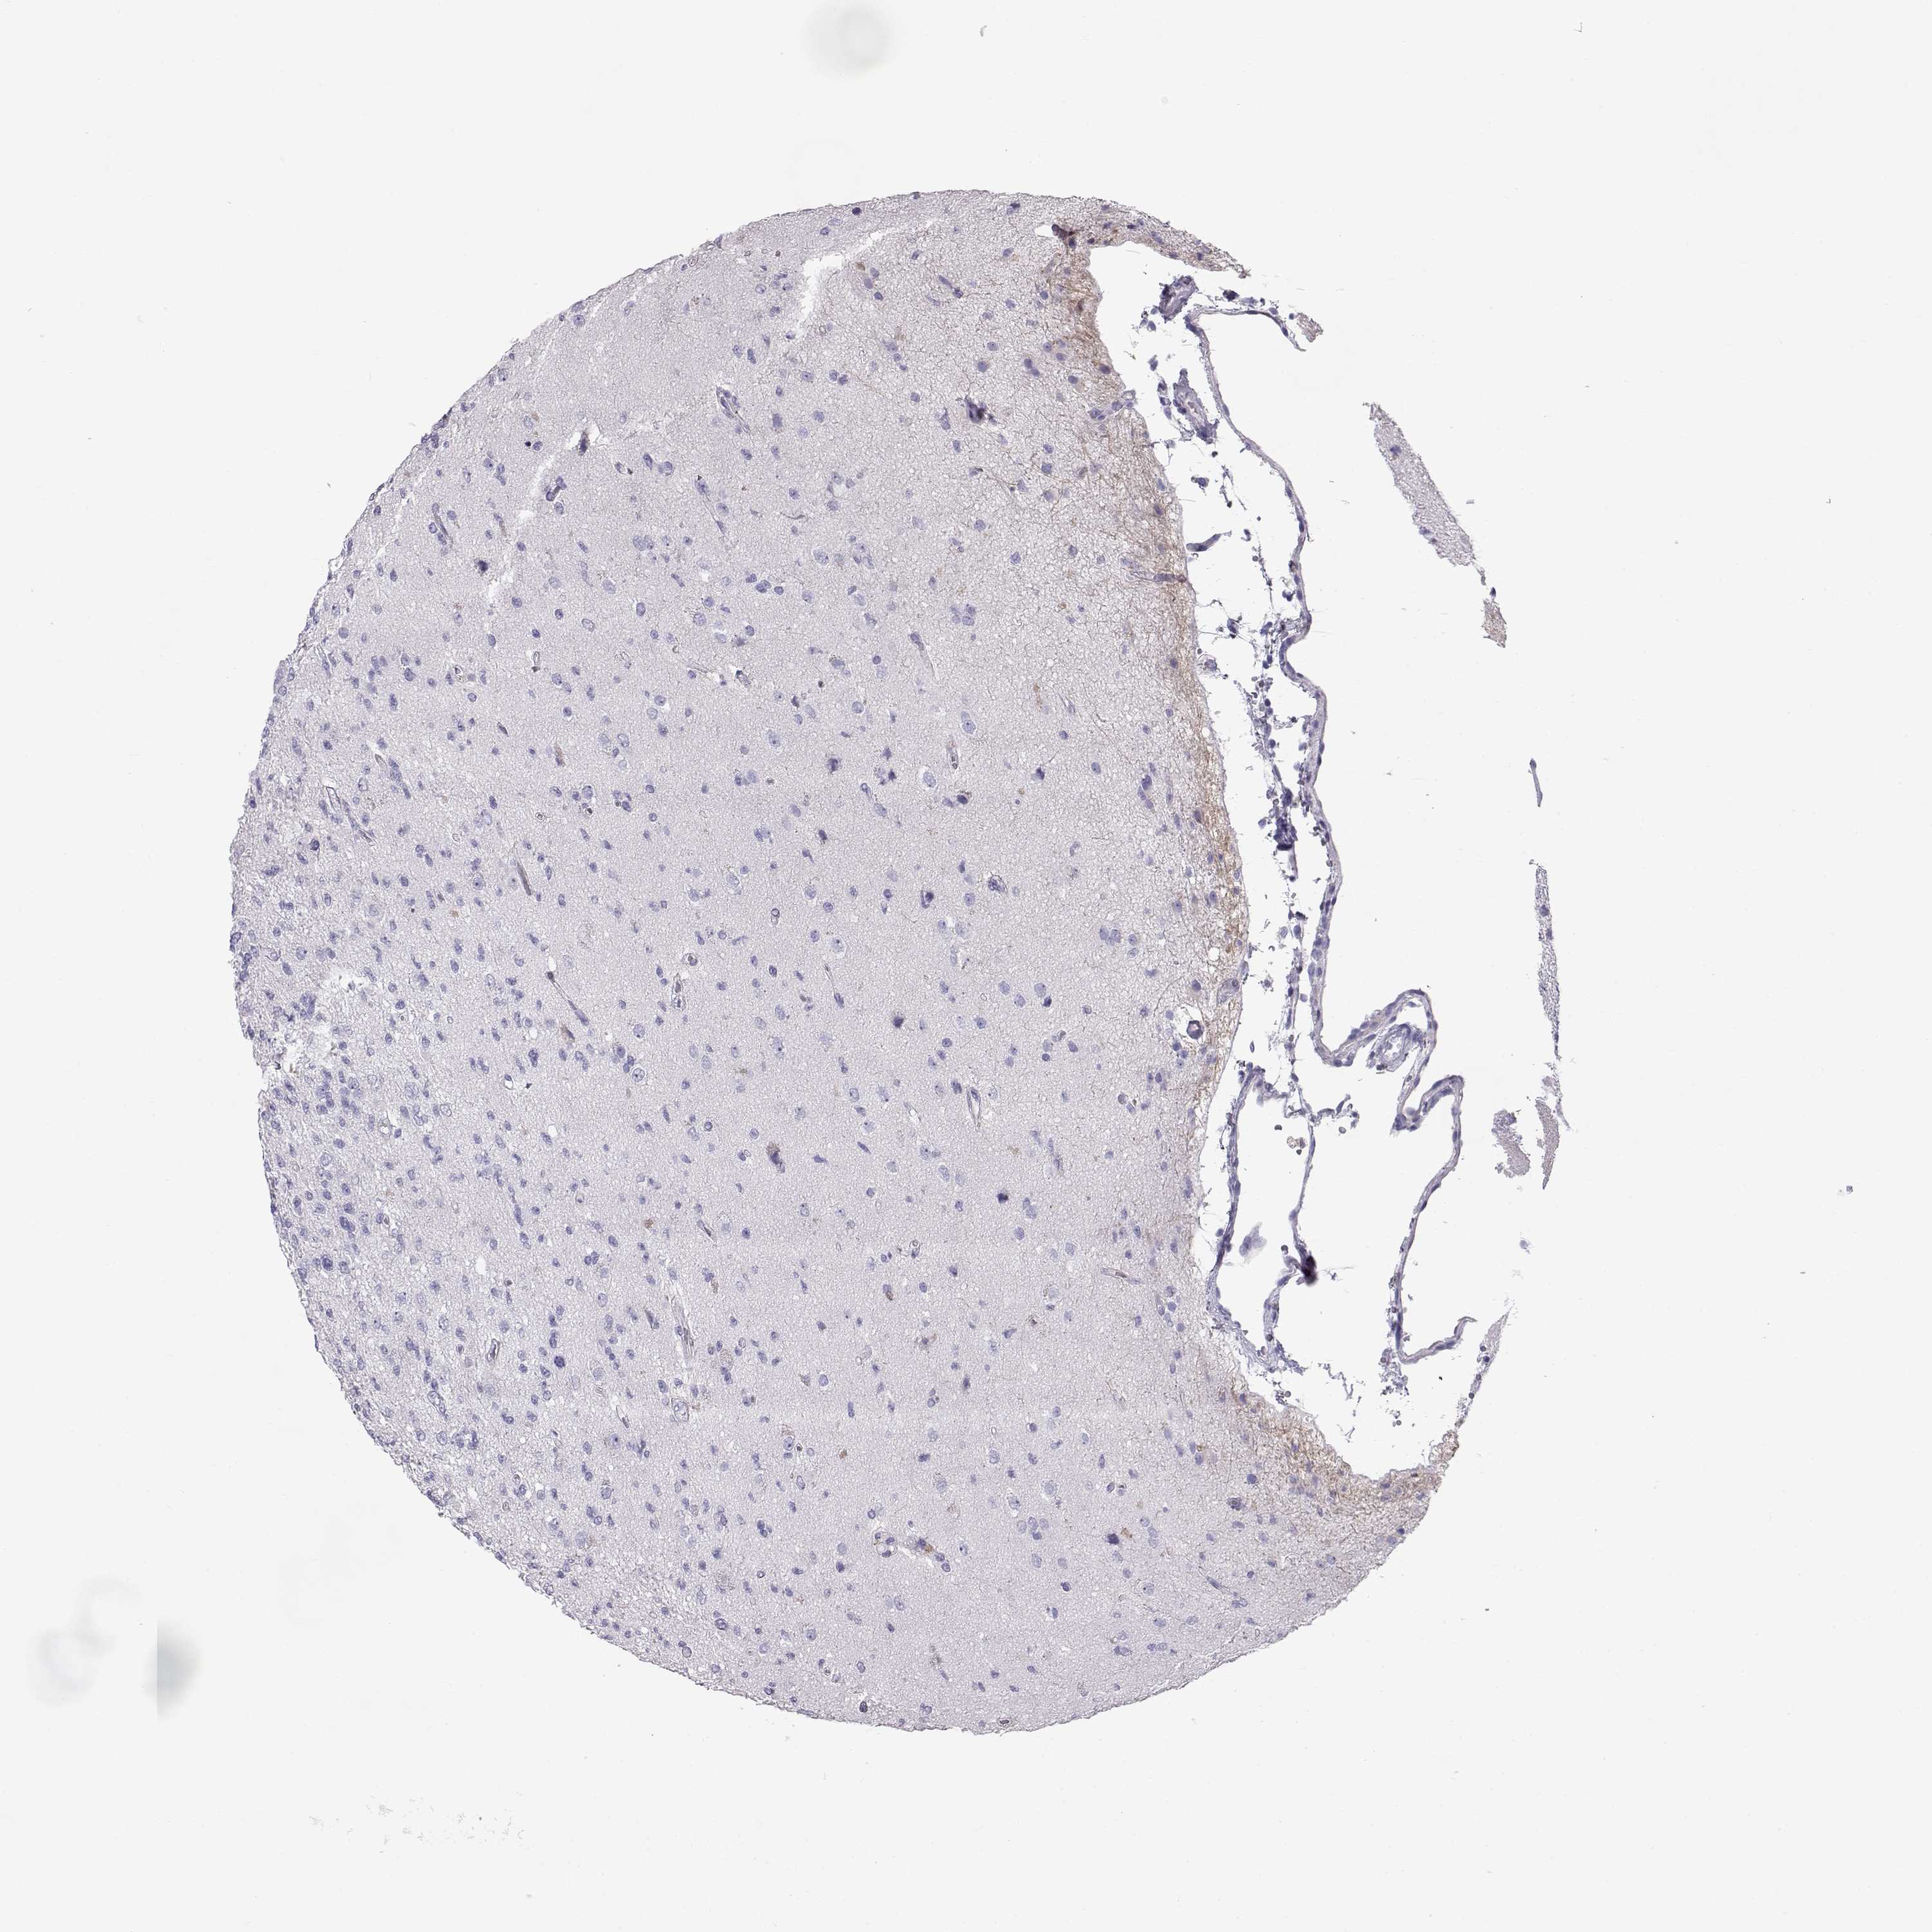

GLIOMA - Protein expressioni

A mouse-over function shows sample information and annotation data. Click on an image to view it in a full screen mode. Samples can be filtered based on level of antibody staining by selecting one or several of the following categories: high, medium, low and not detected. The assay and annotation is described here.

Note that samples used for immunohistochemistry by the Human Protein Atlas do not correspond to samples in the TCGA dataset.

Antibody stainingi

Antibody staining in the annotated cell types in the current human tissue is reported as not detected, low, medium, or high, based on conventional immunohistochemistry profiling in selected tissues. This score is based on the combination of the staining intensity and fraction of stained cells.

Each image is clickable and will lead to virtual microscopy that enables deeper exploration of all samples and also displays staining intensity scores, fraction scores and subcellular localization as well as patient and tissue information for each sample.

Antibody HPA062736

Staining

High

Medium

Low

Not detected

Intensity

Strong

Moderate

Weak

Negative

Quantity

>75%

75%-25%

<25%

None

Location

Nuclear

Cytoplasmic/membranous

Cytoplasmic/membranous,nuclear

Glioma, malignant, Low grade

Glioma, malignant, High grade